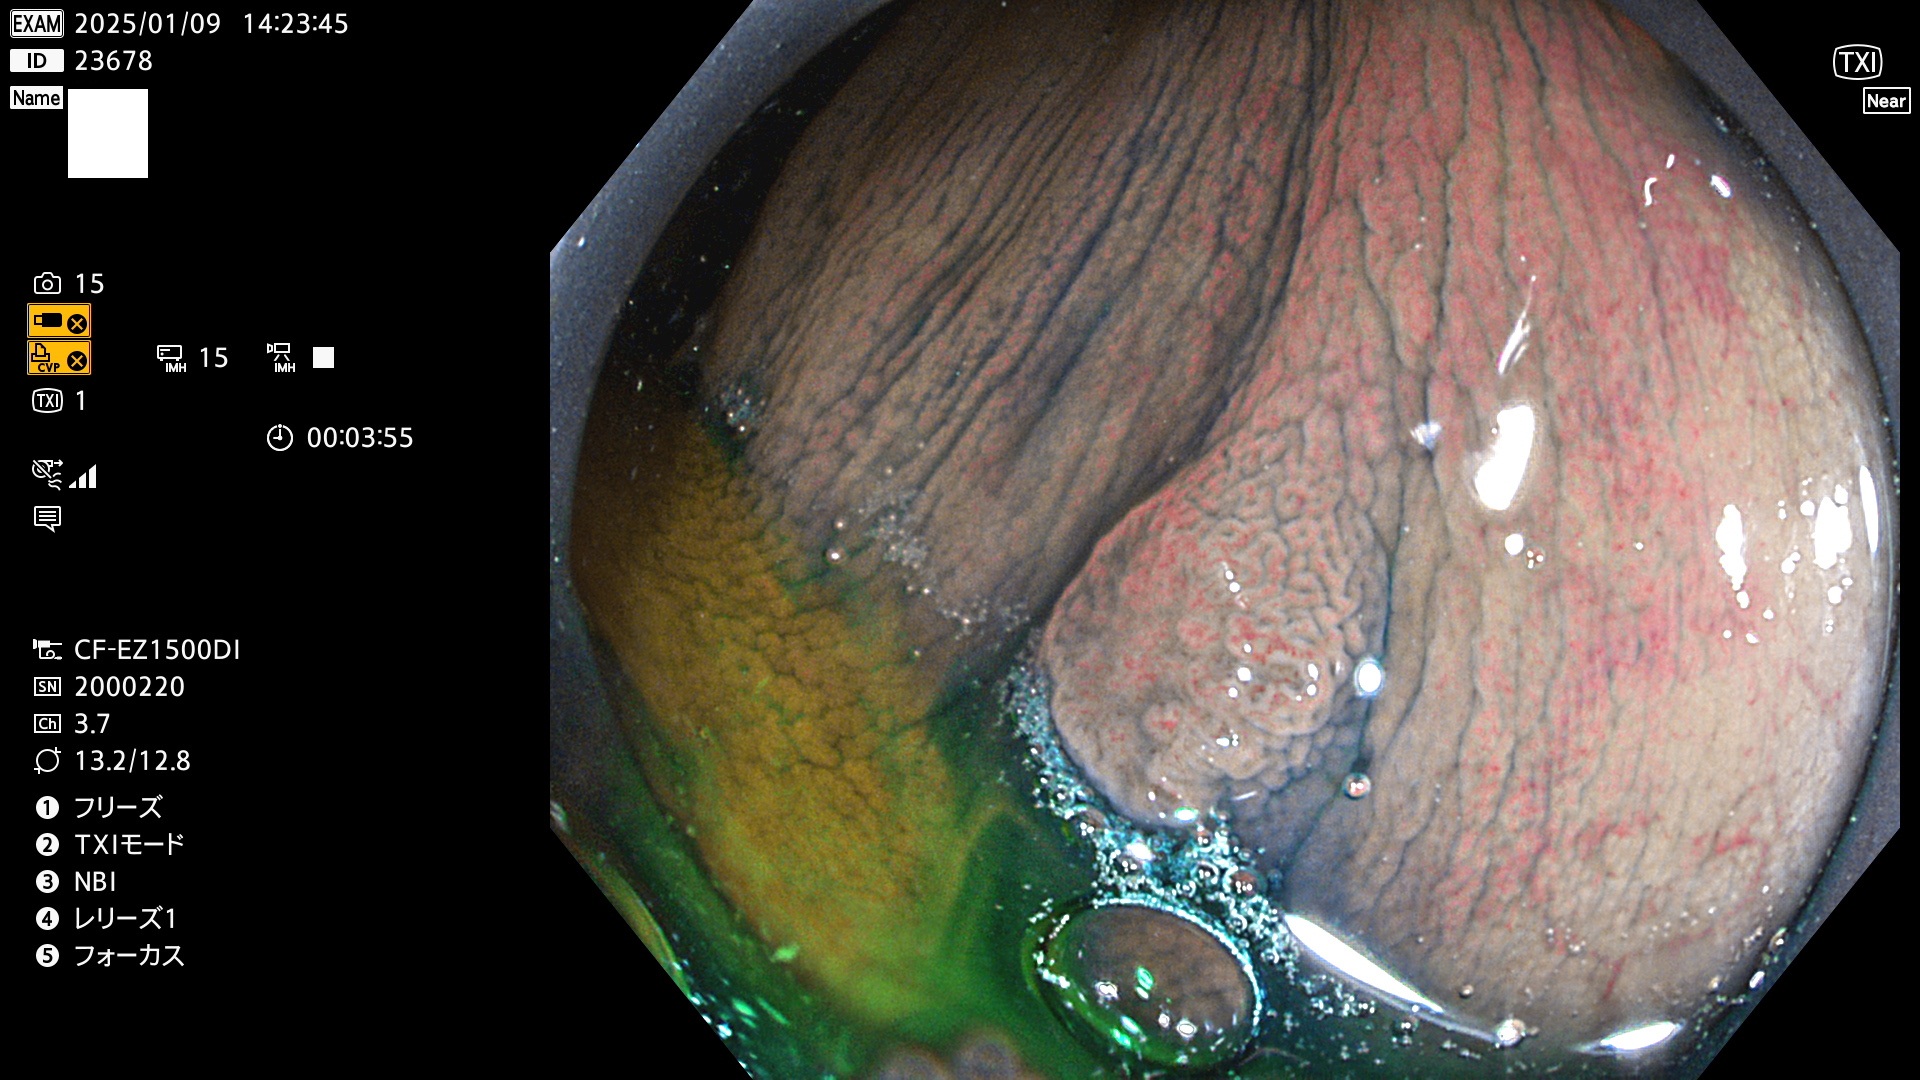

完全に平坦な物をUb、陥凹している物をUcと呼びます。最も発見が難しく危険な病変です。

毎週の検査(木・金・土・日)に発見されたUb、Uc型・腺腫を、その週の日曜の夜にUPし1週間、提示します。

抽出の対象期間 2025年1月9日〜1月12日の4日間(45件の検査)5件 (5/45=11%)